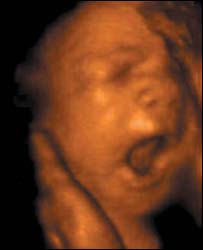

बच्चा 12वें हफ़्ते में अंगड़ाई लेने लगता है

भ्रूण

बारहवें सप्ताह में बच्चा गर्भाशय में 'चलने' लगता है

नए अल्ट्रॉसाउंड स्कैन ने जो तस्वीरें ली हैं उसमें 12 सप्ताह के भ्रूण को गर्भाशय में 'चलते' हुए देखा जा सकता है.

इतना ही नहीं नए स्कैन से यह भी देखा जा सकता है कि माँ के पेट में बच्चा किस तरह जम्हाई लेता है और किस तरह अपनी आँखें मलता है.

लंदन के क्रिएट हेल्थ क्लिनिक में प्रोफ़ेसर स्टूअर्ट कैम्पबेल ने यह नई स्कैन मशीन विकसित की है और इसमें आम स्कैन मशीनों की तुलना में ज़्यादा स्पष्ट तस्वीरें देखीं जा सकती हैं.

त्रि-आयामी चित्र

सामान्य स्कैनिंग मशीन से 12 से 20 सप्ताह तक के गर्भस्थ शिशु की हलचल की तस्वीरें रिकॉर्ड की जा सकती हैं लेकिन वे द्वि-आयामी होती हैं.

नई मशीन गर्भस्थ शिशु की हलचलों की तस्वीरें लेता है

प्रोफ़ेसर कैम्पबेल ने जो मशीन तैयार की है वह न केवल त्रि-आयामी तस्वीर लेती है बल्कि उसे उसी समय रिकॉर्ड भी कर लेती है.

उन्होंने जो तस्वीरें खीचीं हैं उनमें देखा जा सकता है :

- 12 सप्ताह का भ्रूण अंगड़ाई लेता है और हाथ पैर चलाने लगता है, हालांकि तब तक माँ को बच्चे की गतिविधियों का पता नहीं चलता है.

- 18 सप्ताह का भ्रूण अपनी आँखें खोलने लगता है, अब तक डॉक्टर मानते थे कि भ्रूण जब तक 26 सप्ताह का नहीं हो जाता वह अपनी आँखें नहीं खोलता.

-26 सप्ताह का बच्चा किसी बच्चे की ही तरह हरकतें करने लगता है, मसलन वह मुस्कुराता है, रोता है, हिचकियाँ लेता है, खुजलाता है और अंगूठा चूसता है.